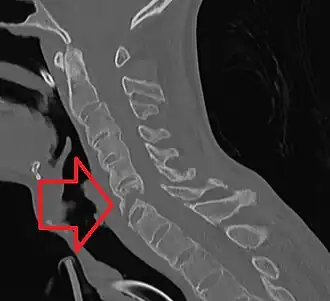

Перелом позвоночника — патологическое состояние, возникающее в ходе нарушения анатомической целостности костей позвоночника. Происходит под воздействием силы, вызывающей резкие и чрезмерные сгибания позвоночника или при непосредственном воздействии силы (травма). Все переломы позвоночника можно разделить на ряд групп в зависимости от положения перелома и его характера:[2]

- Перелом шейного отдела позвоночника

Повреждения нижнего шейного отдела позвоночника

В этой части рассмотрены повреждения, которые чаще всего отмечаются на уровне с C3 до C7 позвонков.